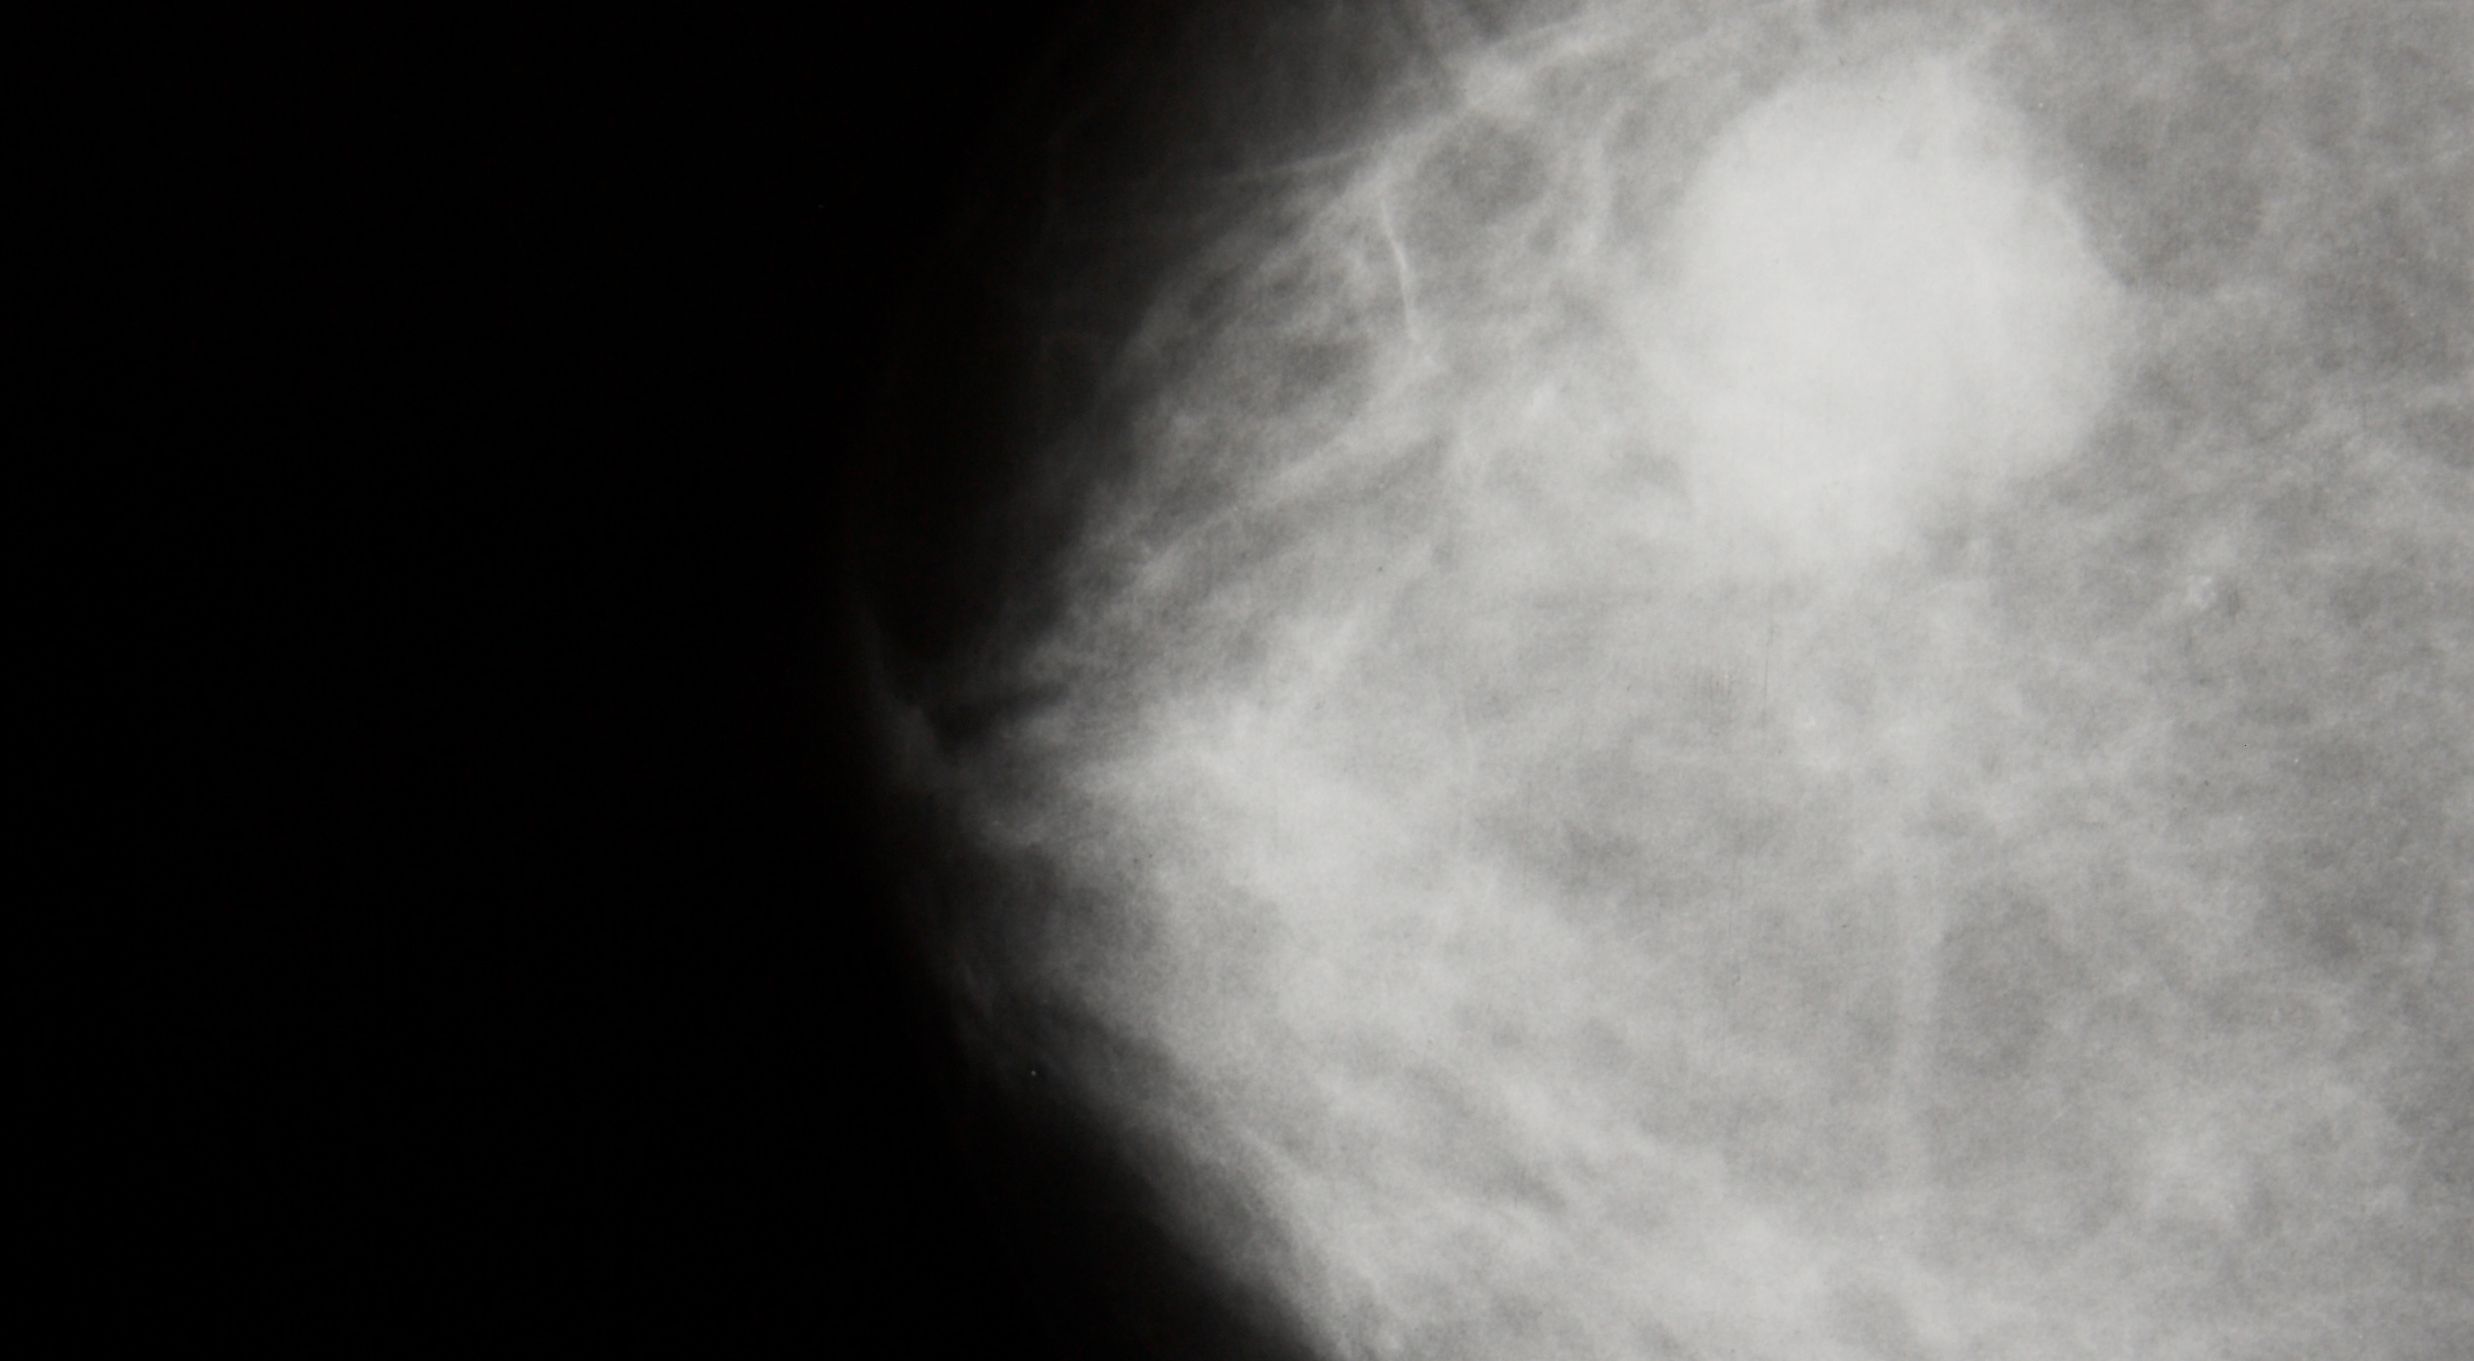

Breast Cancer